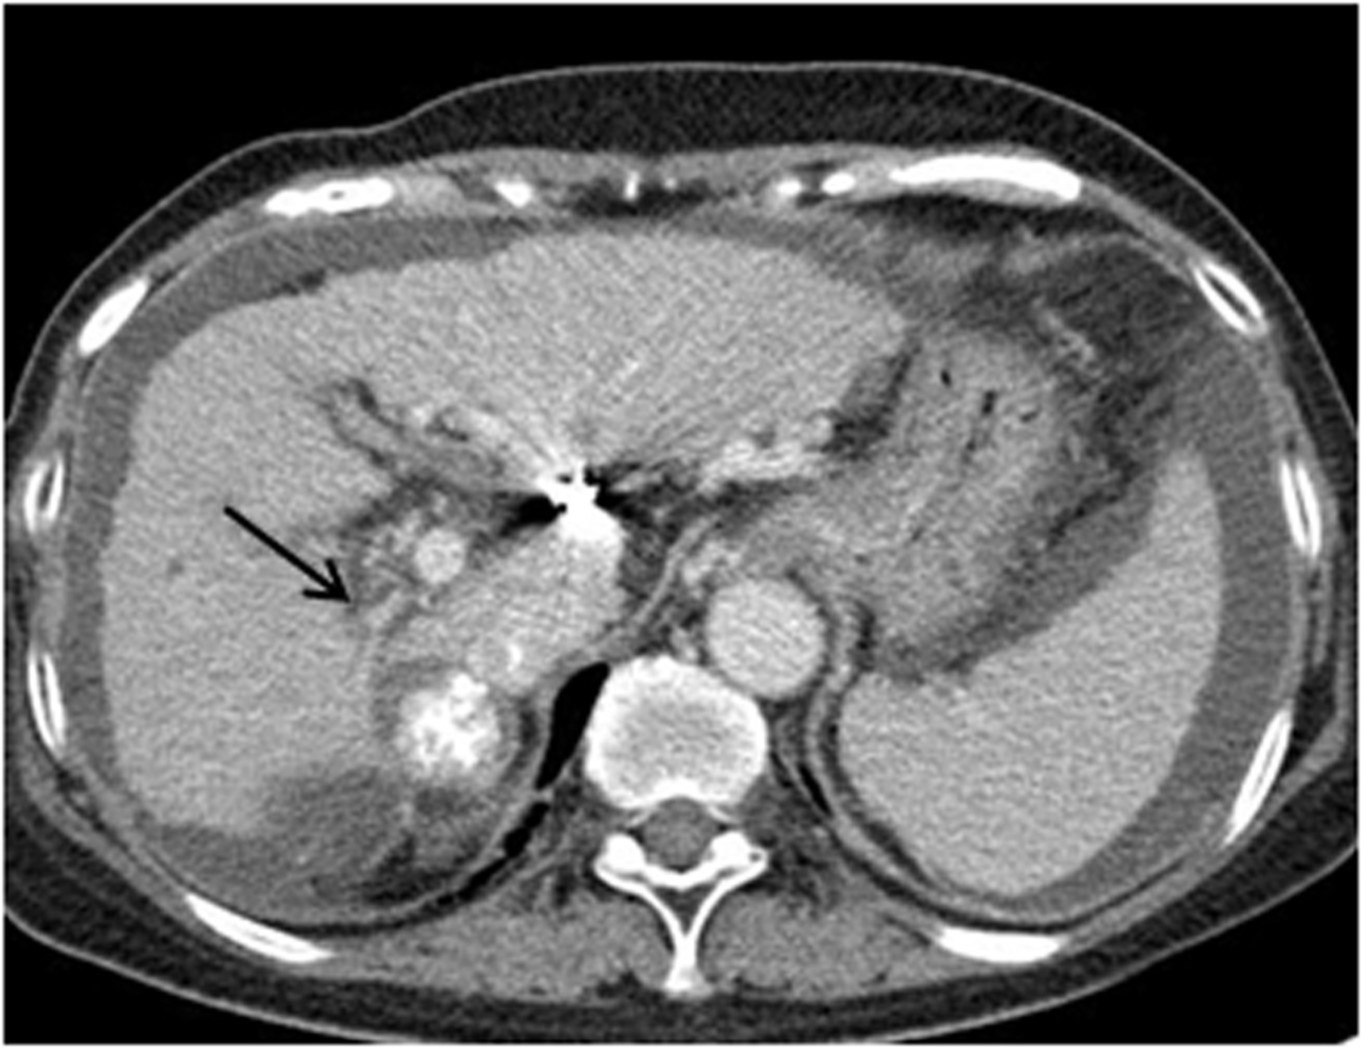

Liver의 Segment 7에 lipiodol uptake된 HCC가 보이고, right hepatic lobe의 atropic change 와 right portal vein의 narrowing이 보인다 (Fig.1).

Fig. 1. Portal phase of contrast enhanced CT scan shows atrophic change of the right hepatic lobe and narrowing of the right portal vein(arrow). Lipiodol laden HCC mass is seen near the right portal vein.